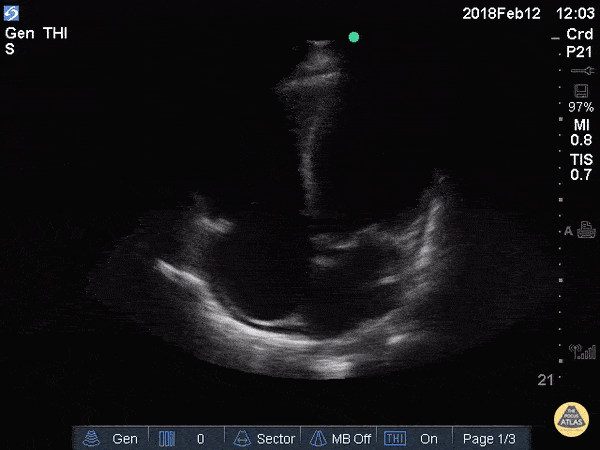

Left Ventricular Dysfunction - Reduced EF (Apical 4 Chamber)

An elderly gentleman with non-ischemic cardiomyopathy 2/2 meth use and a very poor EF. EPSS was 2.21 when measured in parasternal long axis correlating with severely reduce ejection fraction. Greg Powell, MD - ULCA/Harbor